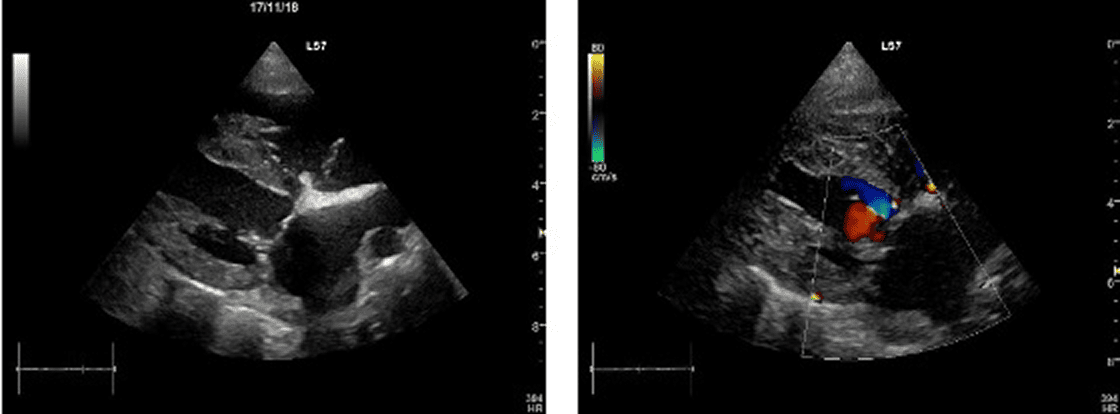

僧帽弁形成術術後

弁尖の位置が正常化し,前尖・後尖の良好な接合が得られたことで逆流が消失している。